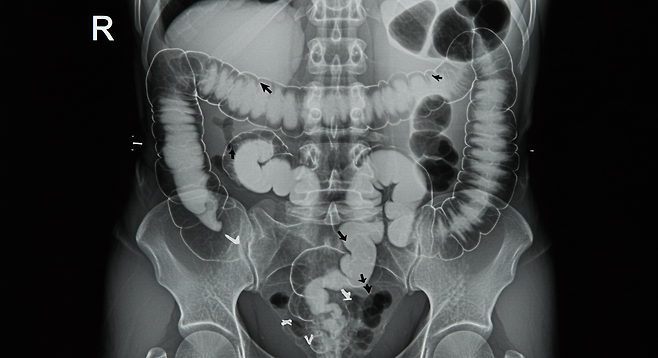

장폐색(腸閉塞)은 장이 막혀 음식물이나 가스가 이동하지 못하는 급성 위장 응급질환입니다. 아래와 같은 전조증상이 나타난다면 즉시 병원 진료를 받아야 합니다.